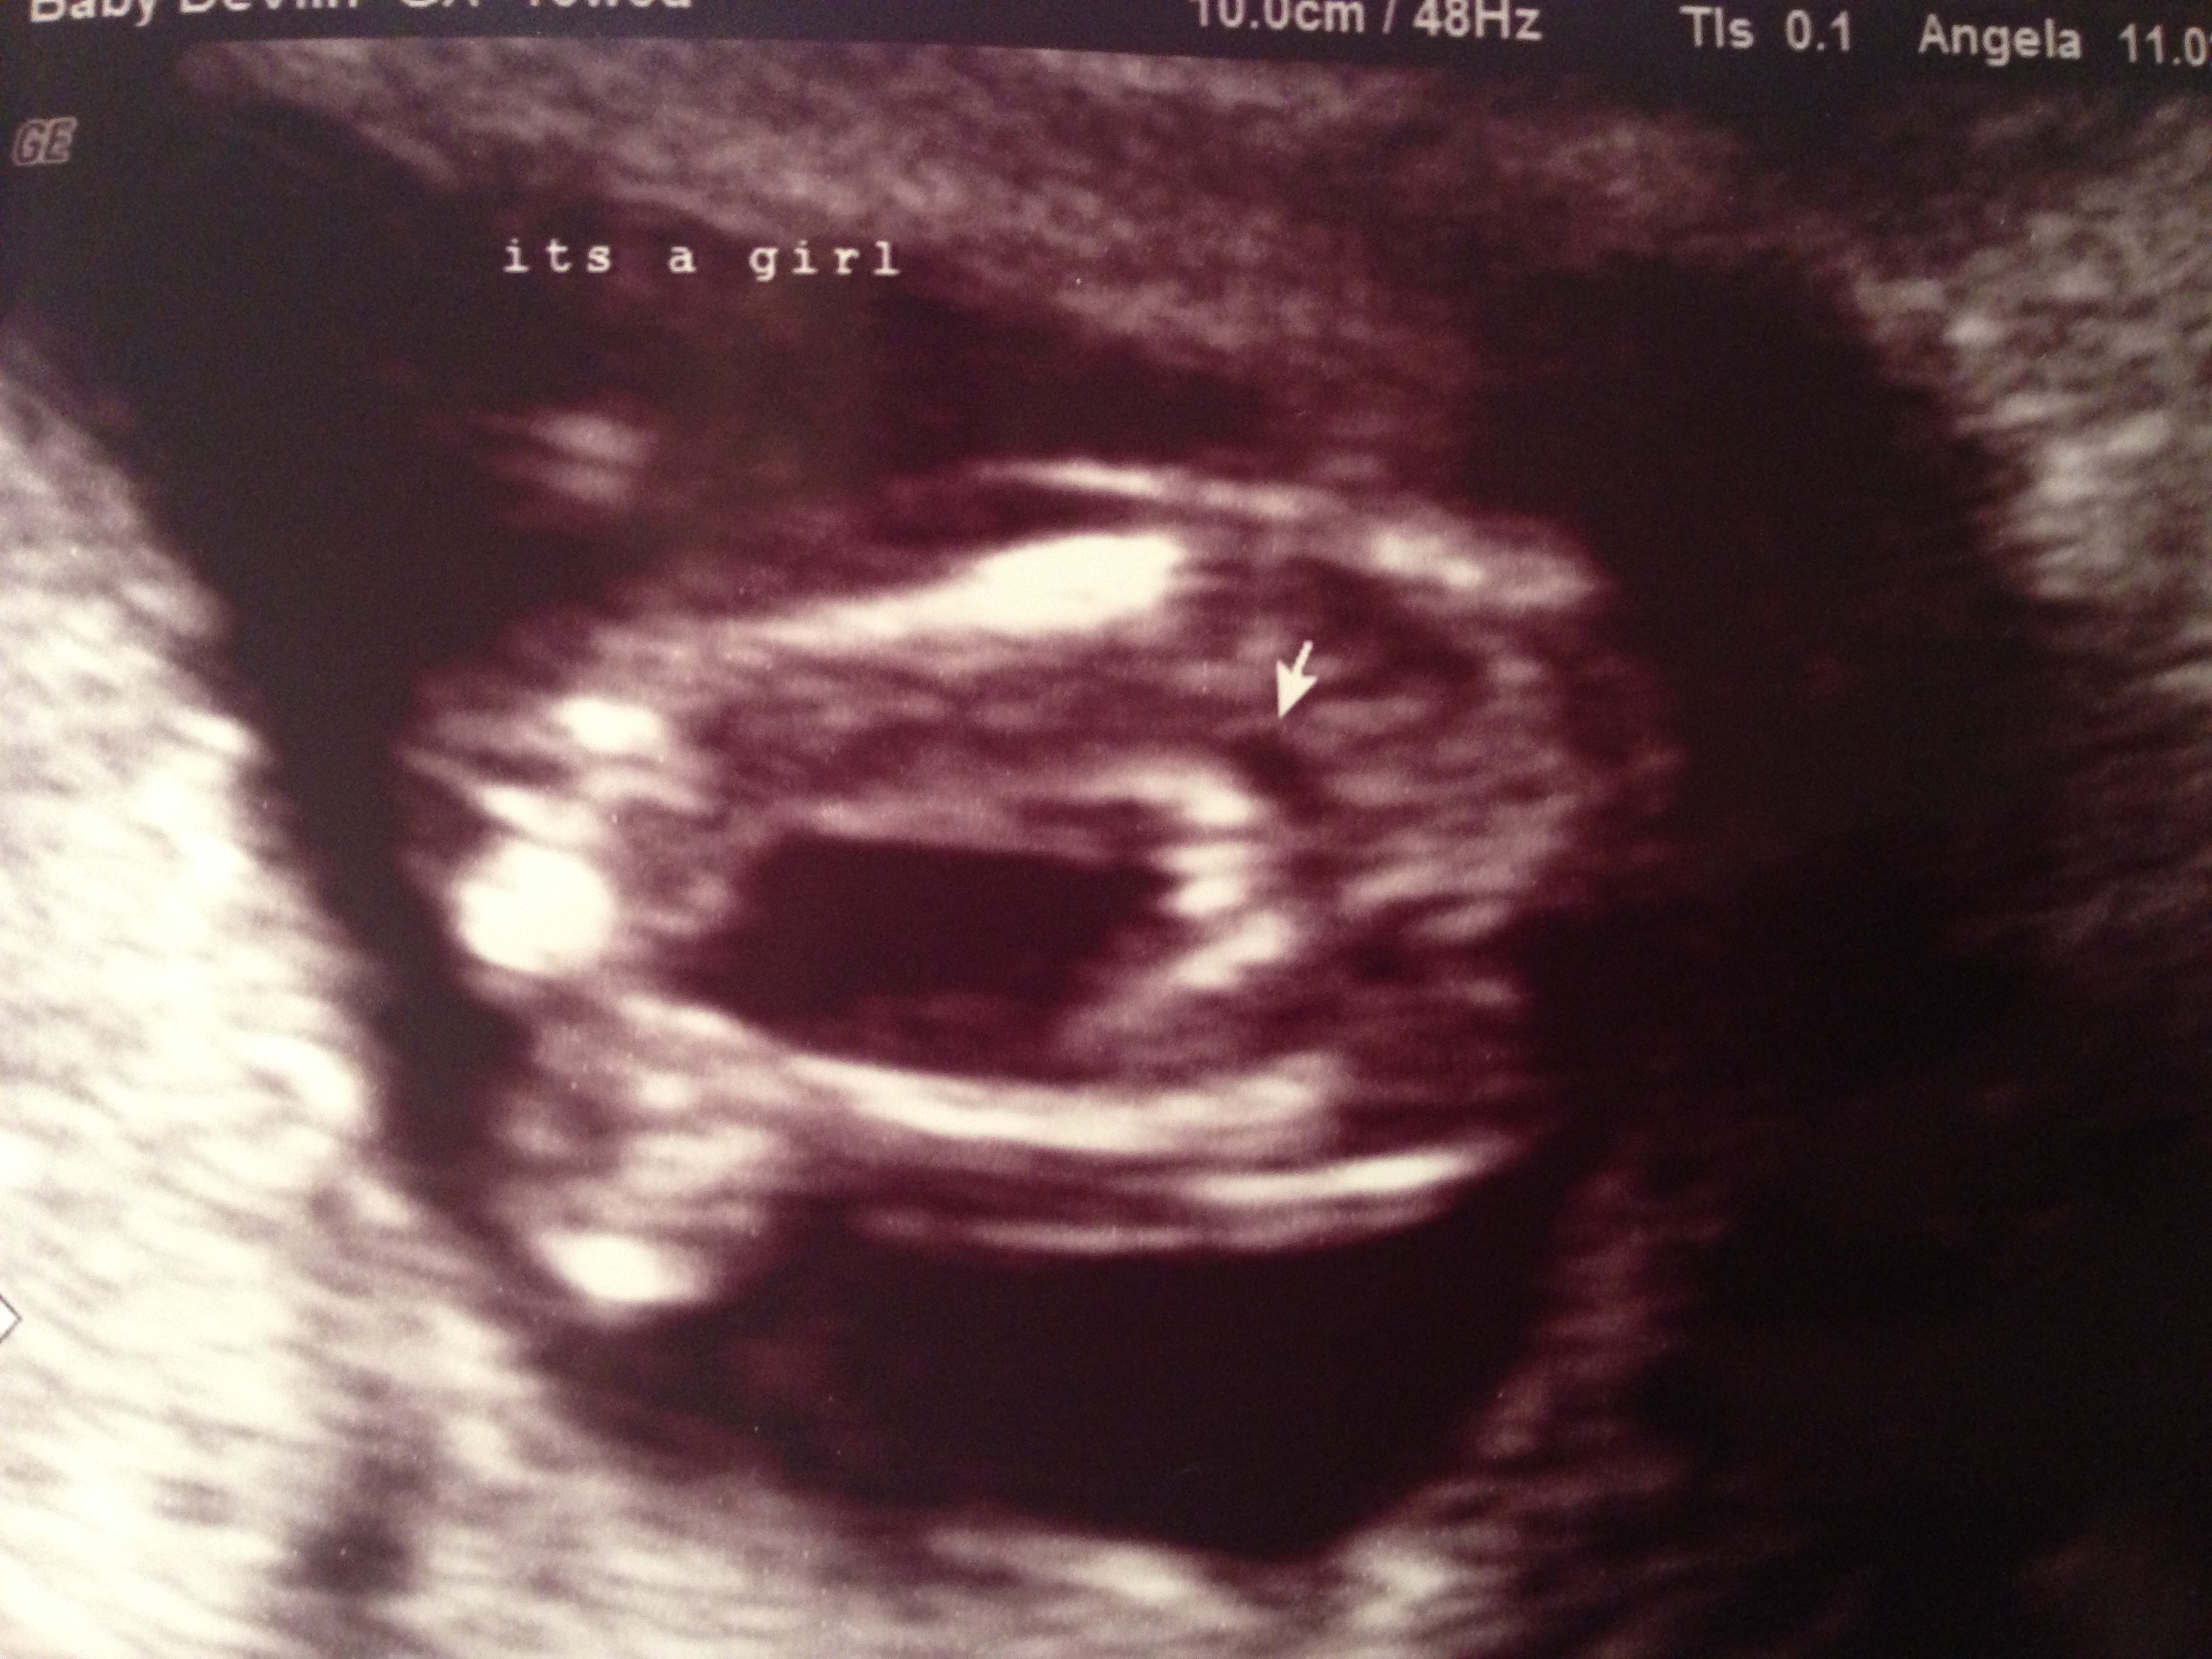

Edited Scan pic lighting to make everything as clear as possible

Maybe a girl but there is the faintest uptilt at the end that makes me not for certain.

Would there be a difference between a slight uptilt only and a slight uptilt with also a slight faint down tilt? Not sure if you see but once zoomed in there is also a faint down tilt bit too?

Confirmed girl at 15+5 :)